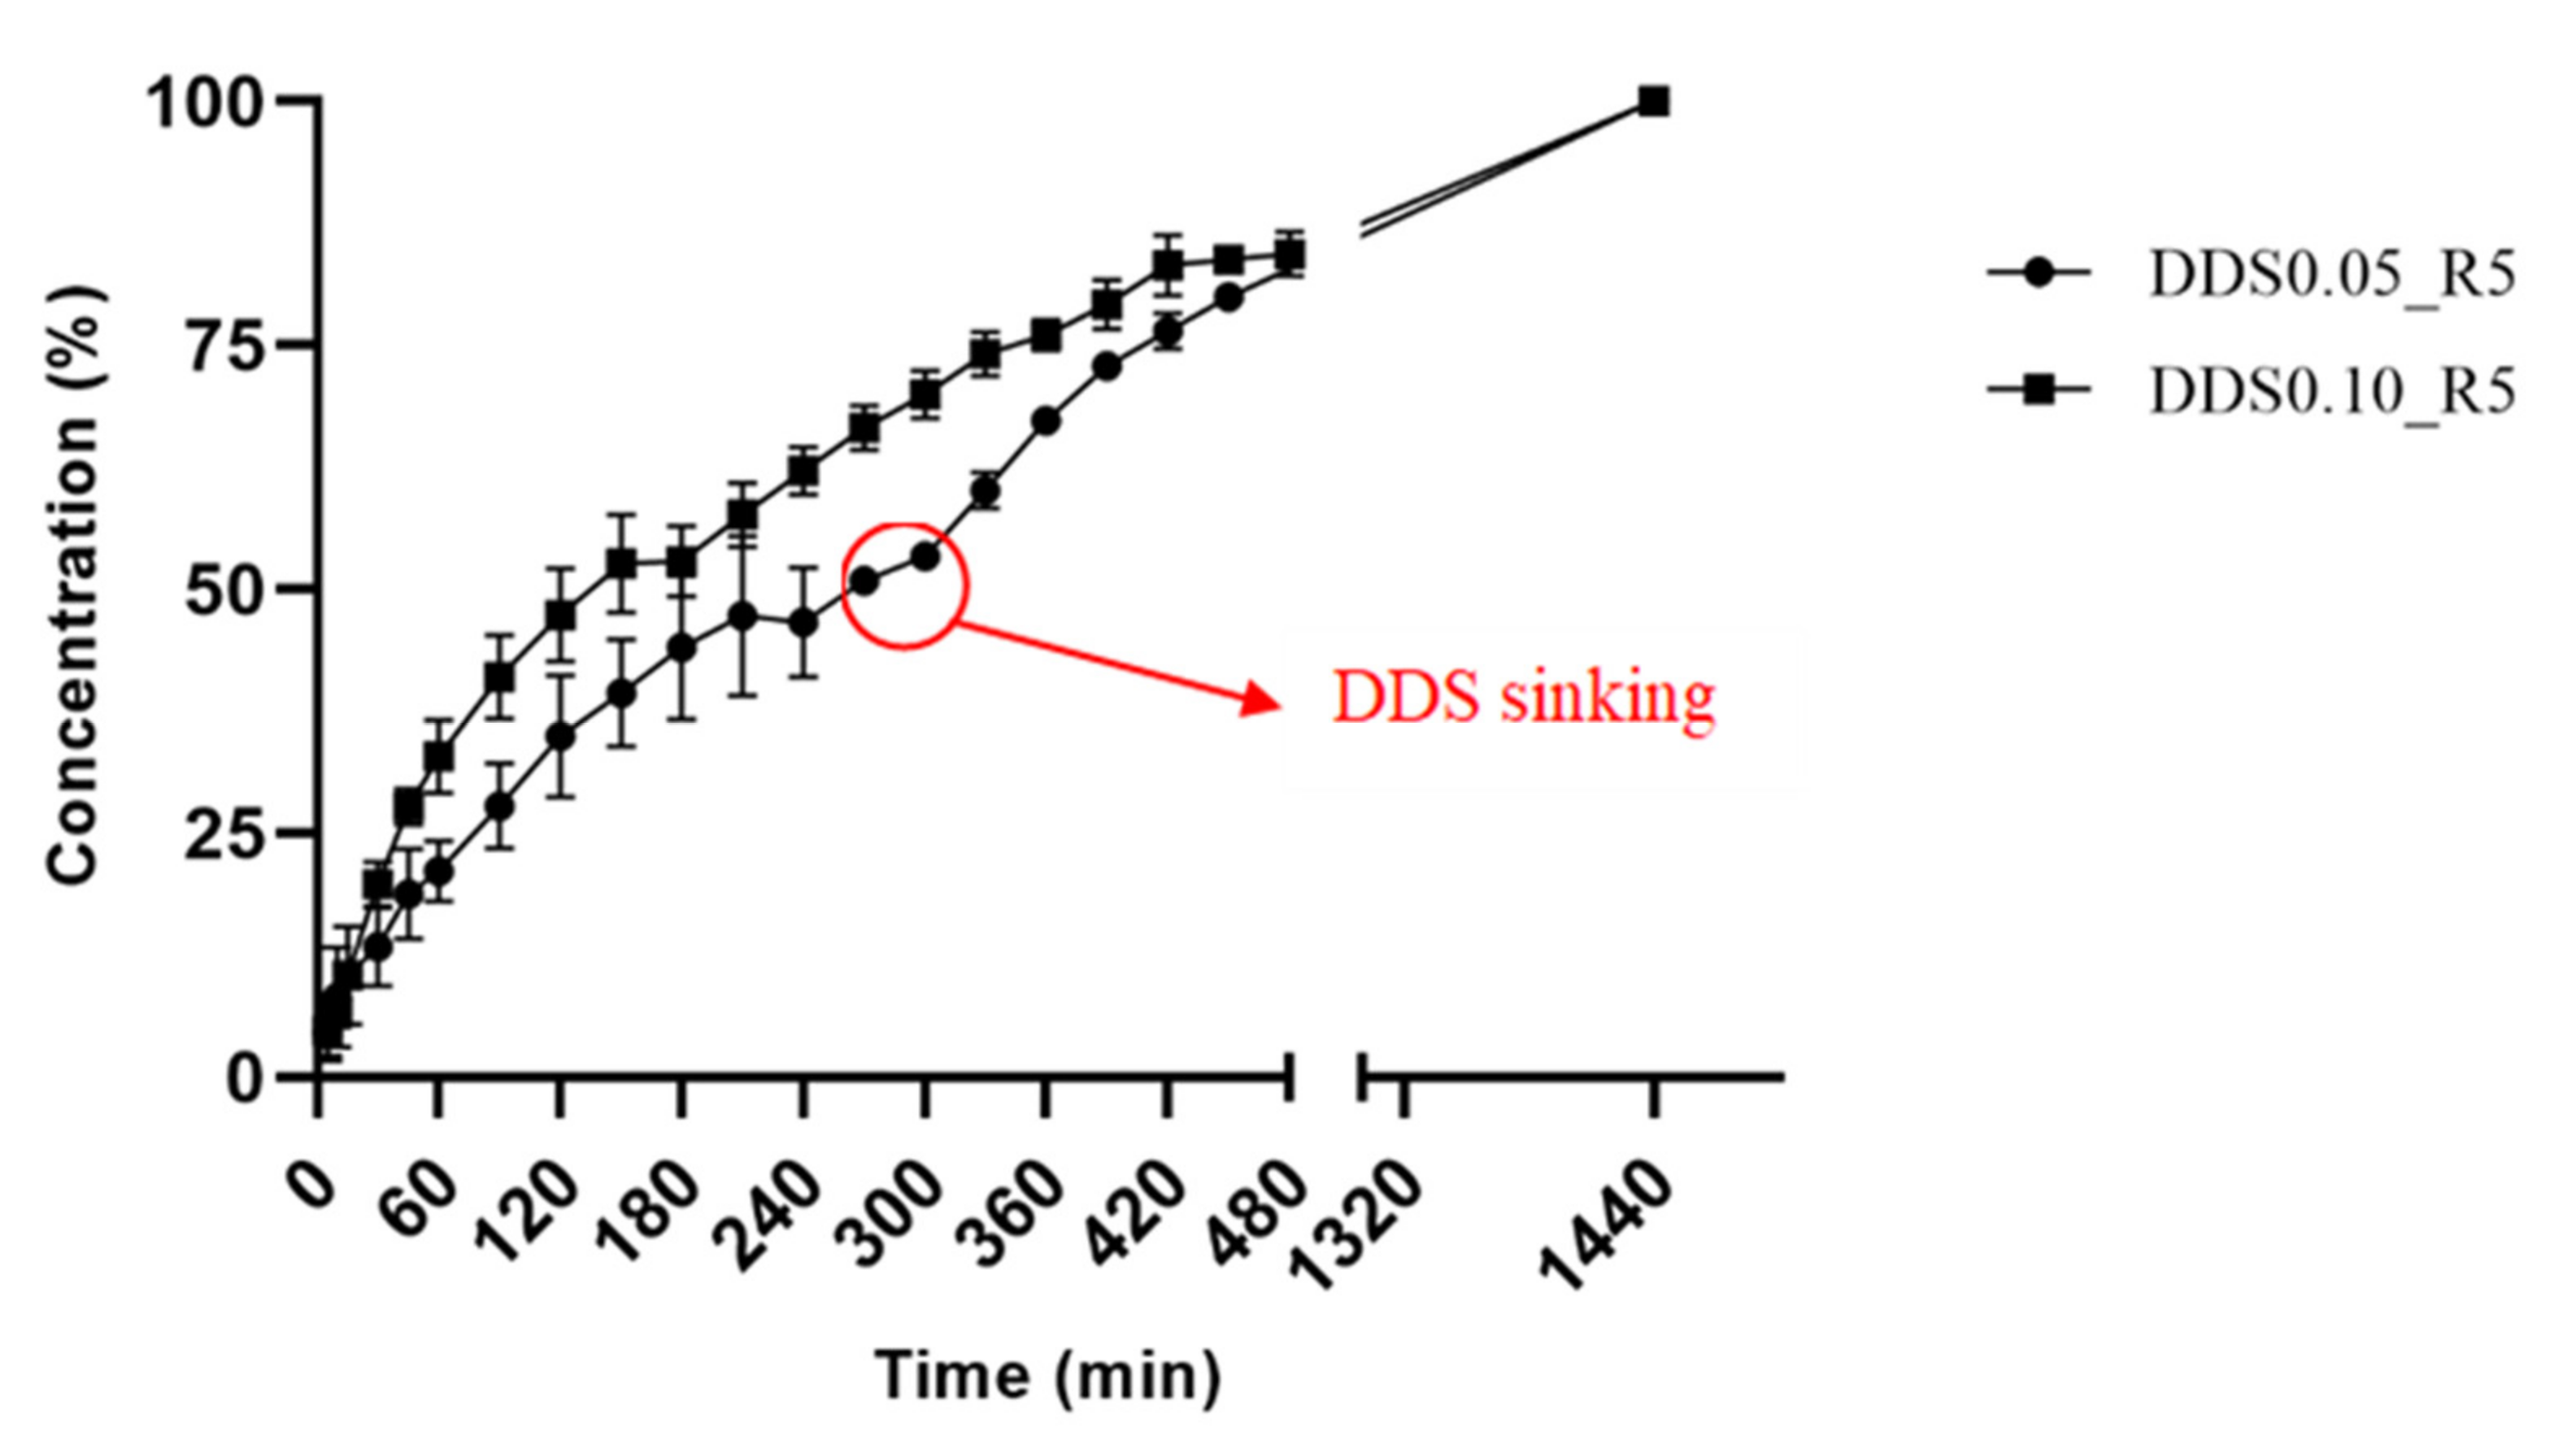

2.8. Buoyancy and In Vitro Drug Release

4.2.10. Buoyancy and In Vitro Drug Release Evaluation